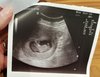

36 mm szczęścia :) dzisiaj mam 10+4. Objawy też mi ustały, czułam się nie ciążowo, dlatego postanowiłam sprawdzić czy wszystko ok. Serduszko bije, bardzo ruchliwe dzieciątko :)

Załączniki

• IMG_20190909_174940.jpg

IMG_20190909_174940.jpg

268,9 KB · Wyświetleń: 126

Zobaczysz, że wszystko będzie dobrze. U mnie serio skończyły się mdłości, ból piersi, okropne zmęczenie, senność. Czuję się jakbym w ciąży nie była. A dzisiaj machała mi taka mała kluseczka. Nie martw się na zapas. Wszystko jest dobrze, wspomnisz moje słowa :)